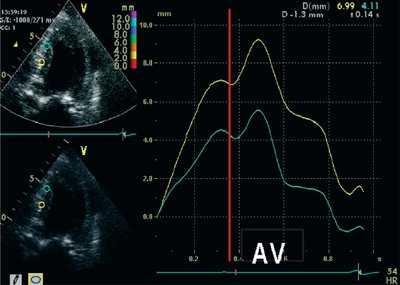

ЭхоКГ (стандартная и в режиме тканевой допплерографии) проводилась на ультразвуковой диагностической системе Vivid Five фирмы General Electric (США) секторным датчиком c частотой 3,75 МГц. Исследовалось движение продольных волокон миокарда в проекциях по длинной оси левого желудочка из верхушечного доступа. Тканевая допплерография проводилась в 4-, 3- и 2-камерной проекциях в каждом из 16 сегментов левого желудочка и в 4 точках митрального кольца: у основания заднеперегородочной, боковой, нижней и передней стенок левого желудочка. Оценивались следующие параметры.

- Пиковые миокардиальные скорости: Sm (см/с) - пиковая систолическая скорость; Em (см/с) - пиковая скорость раннего диастолического расслабления; Am (см/с) - пиковая скорость в фазу систолы предсердий.

- Временные интервалы: систолический (TRS; от вершины зубца R на ЭКГ до вершины пика Sm) и диастолический (TRE; от вершины зубца R на ЭКГ до вершины пика Em).

- Амплитуда систолического смещения миокарда (INT) 1 .

- Пиковая скорость и амплитуда систолической деформации: SR (strain rate) и ST (strain).

Использование тканевой допплерографии при оценке нарушений локальной сократимости в покое

Для того, чтобы оценить возможности тканевой допплерографии при выявлении нарушений локальной сократимости в покое, мы сравнили показатели тканевой допплерографии больных с постинфарктным кардиосклерозом и здоровых лиц. Сегменты больных с постинфарктным кардиосклерозом были разделены на 3 подгруппы по результатам двухмерной ЭхоКГ: нормокинетичные (n=184), гипокинетичные (n=121) и акинетичные (n=104). Дискинетичные сегменты были исключены из анализа вследствие малого их числа (n=4).

В подгруппах сегментов с нарушенной локальной сократимостью при сопоставлении с контрольной группой было выявлено достоверное снижение миокардиальных скоростей как в систолу (Sm), так и в раннюю и позднюю диастолу (Em и Am). Наряду со снижением скоростей в этих зонах отмечалось уменьшение амплитуды систолического смещения (INT), а также скорости и амплитуды систолической деформации (SR и ST). В подгруппе сегментов, где отсутствовал систолический прирост (акинезия), значения скоростных и линейных показателей тканевой допплерографии были достоверно ниже, чем в подгруппе с умеренным снижением сократимости (гипокинезия). Следует отметить, что в подгруппе визуально интактных сегментов у больных с постинфарктным кардиосклерозом также было выявлено небольшое, но достоверное снижение указанных параметров тканевой допплерографии по сравнению с контрольной группой (рис.1).

Рис. 1. Значения основных показателей тканевой допплерографии у больных с постинфарктным кардиосклерозом и в контрольной группе.

Временные интервалы TRS и TRE в гипо- и акинетичных сегментах были достоверно увеличены по сравнению с сегментами контрольной группы (172±59 и 154±53 мс в сравнении со 144±50 мс, p 0,05). Это может объясняться эффектом "подтягивания", который приводит к ложному увеличению скоростных и линейных показателей в зонах гипоакинезии, граничащих с интактным миокардом. У больных с высокой ФВ и небольшим объемом пораженного миокарда "подтягивание " в большей степени влияет на движение постинфарктных зон левого желудочка.

На рис. 3-5 приведены различные варианты ПСУ у больных с постинфарктным кардиосклерозом.

![Тканевая допплерография в норме. У больного с постинфарктным кардиосклерозом регистрируется высокоамплитудный пик постсистолической скорости (Sps)]()

Вертикальная линия (AV) на рис. 3-5 соответствует времени закрытия аортального клапана. На представленных графиках также отмечается наличие базально-верхушечного градиента (снижение пиковых миокардиальных скоростей, продольного систолического смещения и деформации от основания к верхушке левого желудочка).